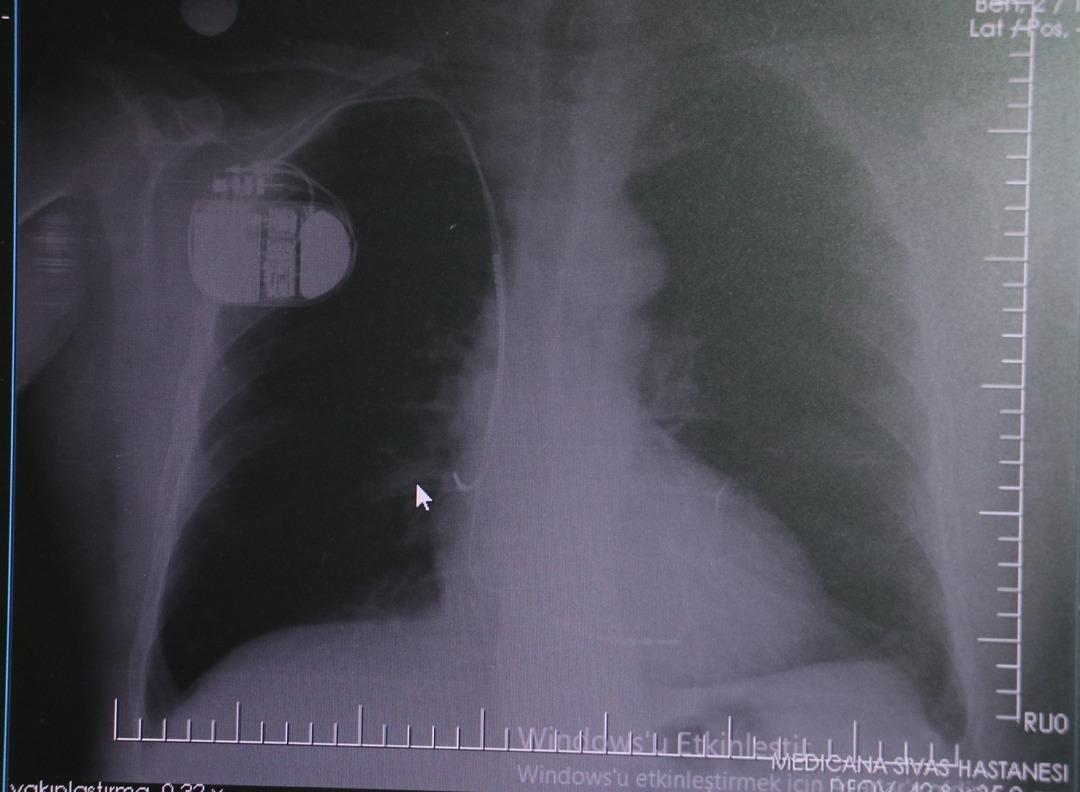

Kalp krizi sonrası kalp dokusunun zarar gördüğünü belirten İsmail Erdoğu, şöyle konuştu: “Kalp hastalığı günümüzde dünyada en sık görülen ölüm nedenlerinden biridir. Kalp hastalıklarının pek çok grubu vardır. Kalp hastalığı dediğimizde sadece kalpte stent bulunan ve damar sorunları olan kişileri kastetmiyoruz. Aynı zamanda hipertansiyon ve şeker hastalığı olan hastalar da kalp hastalığına adaydır. Toplumun yaklaşık %30-35’ini kapsıyoruz. Oldukça yaygın bir hastalıktır ve bu konuda teknolojik ve tıbbi anlamda ciddi gelişmeler yaşanmıştır. Son 30 yılda insanlar kalp rahatsızlığı nedeniyle hastaneye kaldırıldı.” “Hastaneye yattıktan sonra hayatta kalmak artık mümkün. Kalp krizinden kurtulmanın belli bir maliyeti var. Kalp krizinden sonra kalp yetmezliği ortaya çıkıyor. Kalp yetmezliği olan hastalarda aritmiler, ani ölümler gibi sorunlar ortaya çıkabiliyor. Hastaların bu uzun vadeli rahatsızlıklardan kendilerini korumak için mutlaka kalp piline ihtiyaçları var” dedi.

MR makinesine kalp pili takılmasının mümkün olduğunu belirten Erdoğu, şöyle konuştu: “Çok büyük bir ameliyat değil ama yine de ciddi bir cerrahi işlem. Kalp pili tıpta son 30 yılın en büyük gelişmesi. Aslında bilgisayarın minyatürleştirilmiş hali olup insan vücuduna yerleştirilen bir tedavi. İnsan ömrünü önemli ölçüde uzatan bir tedavi. İnsanlar şokla hayata tutunurken, pil olmasaydı öleceğini düşündüğümüz çok sayıda hastamız var. Bu özelliğimiz Kalp pili uygun hastalarda ani ölümü önler, ritmi düzeltecek sağlık çalışanı veya defibrilatör yoksa hastayı hayatta tutmak mümkün değildir. Hastalarımız “kalp pilim var” dediğinde hastalıktan kurtulurlar. Örneğin, mikser kullanmak veya kolu sallayacak herhangi bir hareket kalp pilini olumsuz etkileyebilir. Soğuk havalarda vücutta meydana gelen şiddetli titremeler kalp pilinin hafızasını karıştırıp gereksiz şoklara neden olabilir.